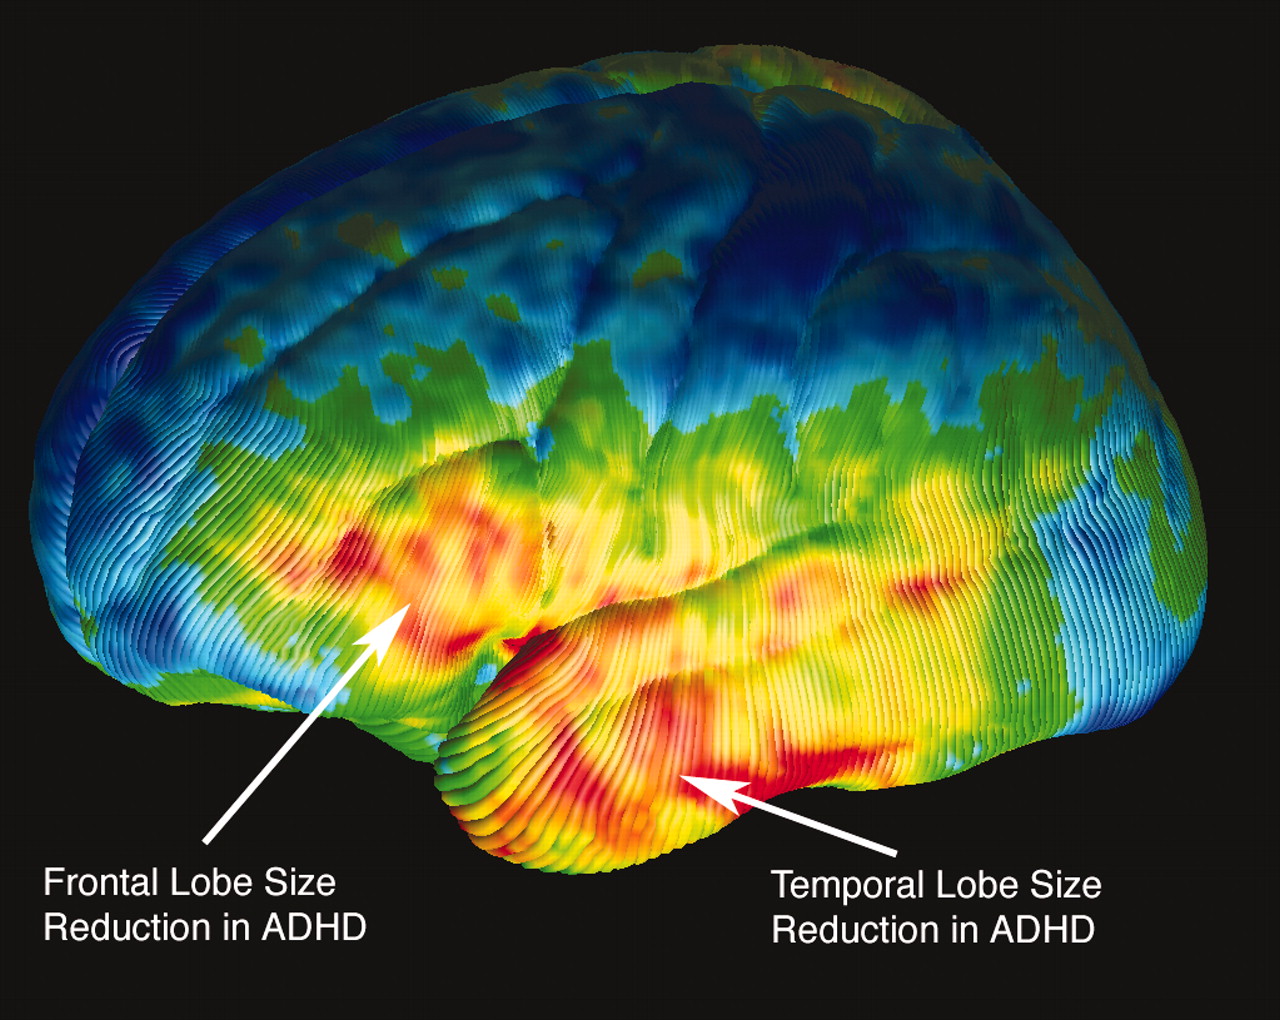

ADHD Brain Vs Normal Brain Functions Differences More

That s why it s vital to stagger the bloom times of your perennials for non stop color Use this list of spring summer and fall blooming perennials for sun and shade to start planning ADHD Brain Vs Normal Brain Differences Explained Unlike summer annuals that bloom consistently over many months, perennials generally have a window of time when their flower flushes appear. By following this guide, you can design a perennial garden that will provide four seasons of interest.

ADHD Brain Differences Stuff4Educators

Adhd Vs Normal Brain Brain Patterns Put Adhd In Focus Australasian